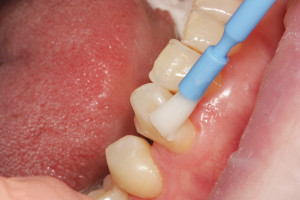

Po wypłukaniu jamy ustnej przez pacjentkę rozcieńczonym eludril classic przystąpiono do fluoryzacji preparatem clinpro varnish. Odizolowano wałeczkami ligniny zęby od śliny aby zapewnić ich suchość, a następnie pędzelkiem nałożono preparat na wszystkie zęby:

Celem fluoryzacji jest zmniejszenie nadwrażliwości zębów oraz wzmocnienie ich przez odbudowę mikroubytków szkliwa.